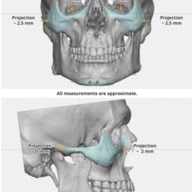

Notice the blue part added in the lf2 diagram.

Instead of doing the big lefort 3 cut, why cant we just add the cheekbone part to the lefort 2?

Instead of doing the big lefort 3 cut, why cant we just add the cheekbone part to the lefort 2?